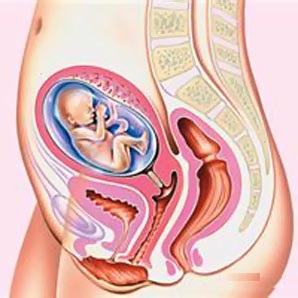

Дитина на 18 тижні вагітності інтенсивно росте, його кістковий скелет зміцнюється. Тому він важить більше, ніж тижнями раніше - близько 250 грам.

УЗД малюка покаже, що він навчився усвідомлено рухатися. Дитина вже вміє піднімати ручки і ніжки, ворушить пальчиками, чіпає ними особа і свої частини тіла. Активні рухи дитини в животі мама тепер дуже добре відчуває.

Протягом обстеження на 18 тижні вагітності можна буде помітити, що дитина освоїв міміку обличчя. Можливо, на УЗД вдасться зафіксувати посмішку малюка або момент, коли він позіхає і смокче пальчик.

Це пояснює тим, що малюк надає на всі органи черевної порожнини і хребет певний тиск, адже матка до цього часу виростає до розмірів маленької дині. Її дно вже розташовано під пупком.